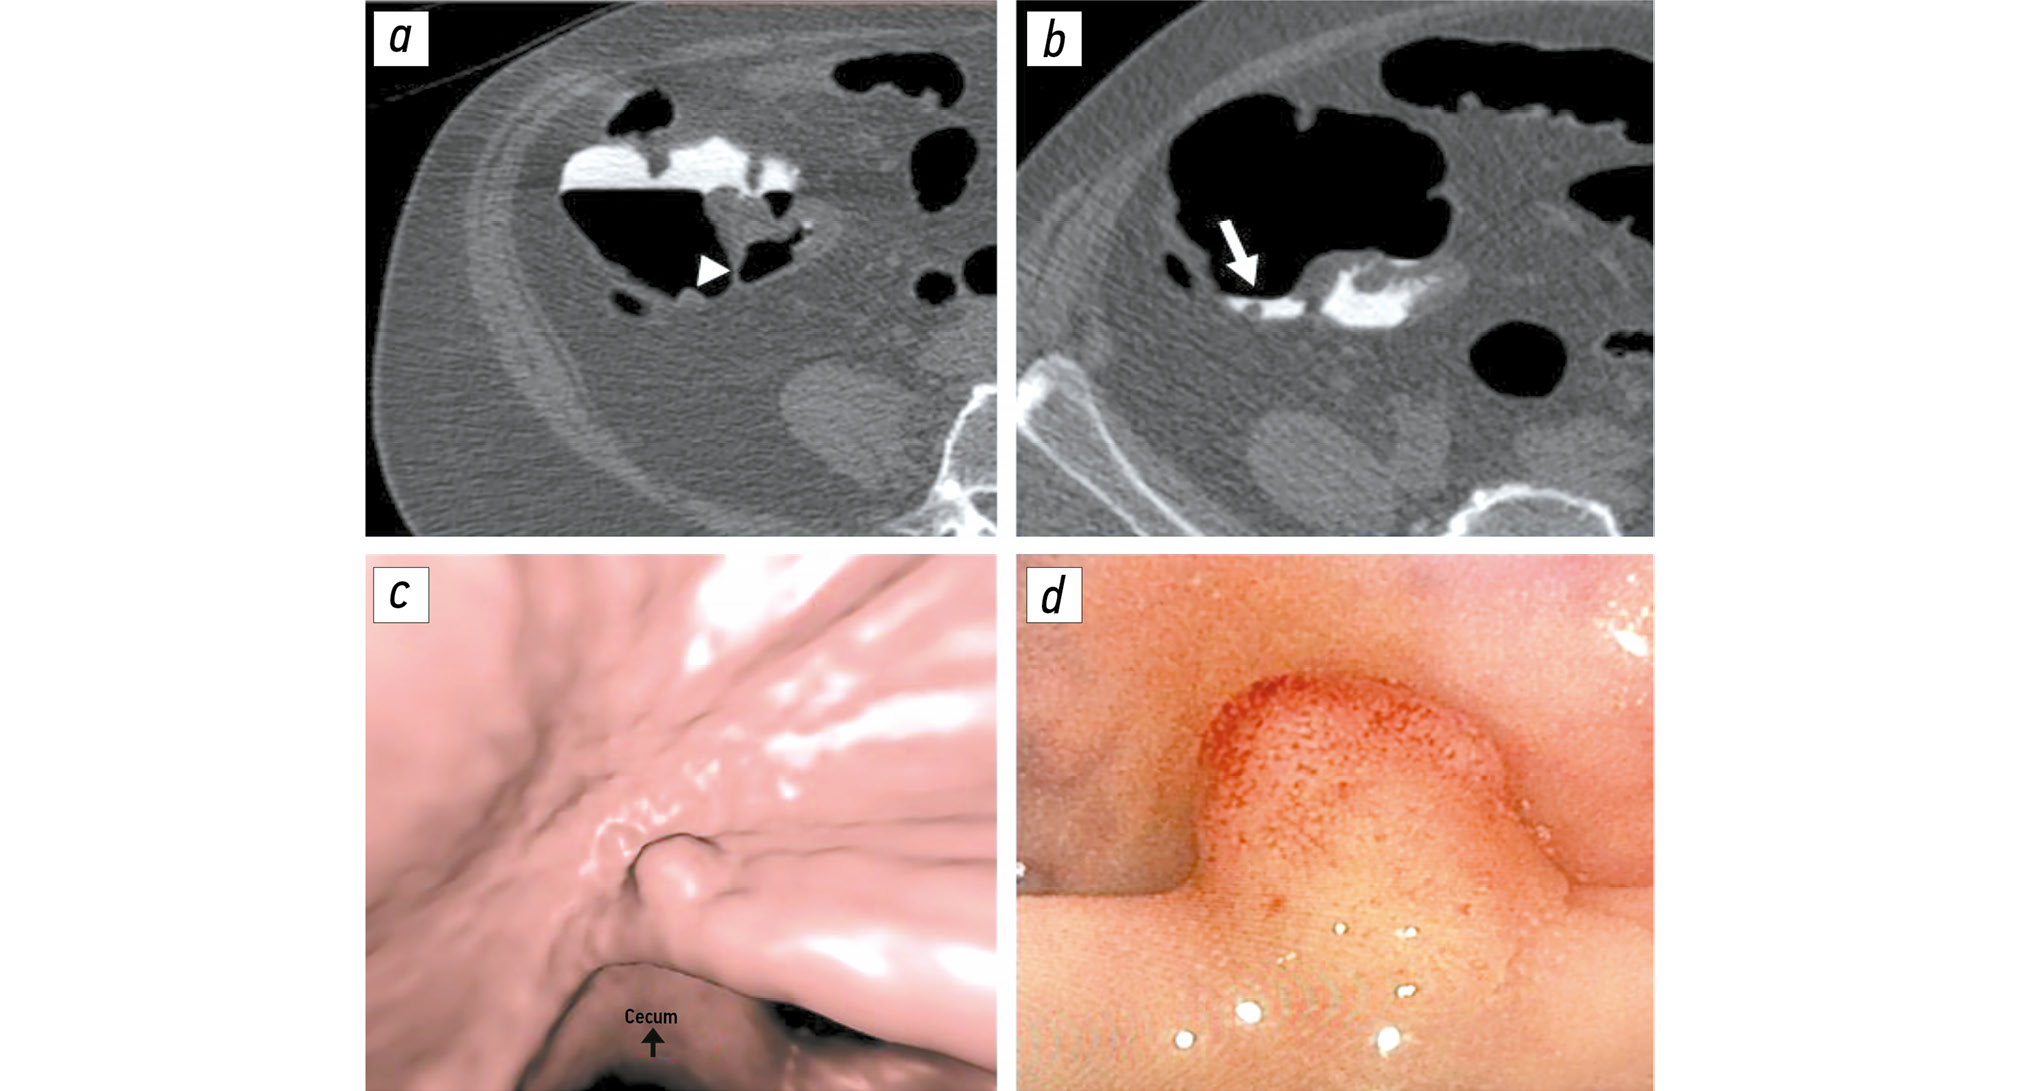

Comparison of single-dose and split-dose fecal tagging with iohexol in computed tomographic colonography

Abstract

BACKGROUND: Proper fecal tagging allows for high-quality computed tomography colonography. However, there is no single tagging scheme. Therefore, the effects of a contrast enhancement regimen on fecal tagging should be evaluated.

AIM: This study aimed to compare the quality of single-dose fecal tagging with that of split-dose fecal tagging with iohexol during computed tomographic colonography and to assess the impact of these regimens on procedure tolerability.

METHODS: In this retrospective, selective, single-center study, the patients were divided into two groups based on whether they received single-dose (group 1) or split-dose (group 2) fecal tagging. Both groups received 50 mL of the iodine-containing contrast agent iohexol, with iodine concentration of 350 mg/mL. The residual liquid density was assessed using three parameters: maximum, minimum, and mean values. Additionally, the residual fluid homogeneity was assessed by calculating the mean standard deviation within the region of interest. Tolerability of preparation for colonography was assessed using a 10-point visual analog scale.

RESULTS: The final sample included 338 patients: 116 in group 1 and 222 in group 2. The mean, minimum, and maximum density values in group 2 were significantly higher than those in group 1: 943 [722; 1245], 753 [525; 1082], and 1079 HU [801; 1456] versus 681 [420; 907], 570 [374; 820], and 825 HU [496; 1154], respectively (p < 0.001). The residual fluid homogeneity was significantly higher in group 2 than in group 1: 59 [46; 78] versus 67 HU [54; 81] (р = 0.012). Group 2 showed a significantly lower subjective difficulty of preparation than did group 1: 4 [2; 6] and 5 [4; 7], respectively (p = 0.004).

CONCLUSION: A single dose of 50 mL of iohexol (iodine concentration: 350 mg/mL) provides higher-quality fecal tagging than a split-dose provides because of higher residual fluid density with maintained homogeneity. Moreover, single-dose tagging was found to be more tolerable.

452-463